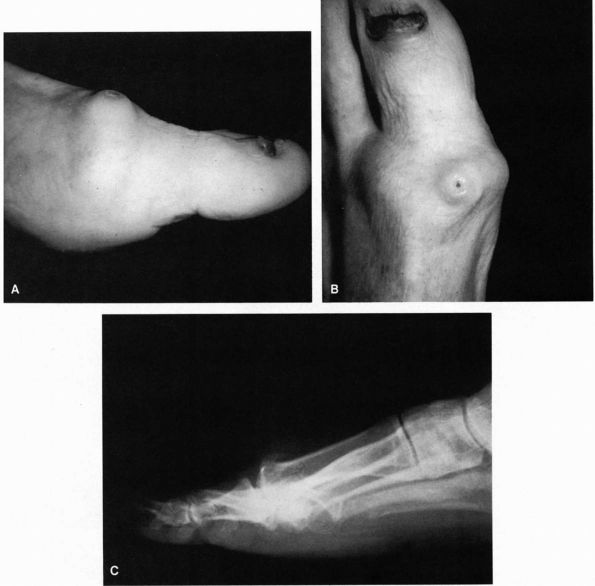

![]() |

FIGURE 21-9. (A and B)

is a common problem. These patients develop a large dorsal osteophytic

ridge on the metatarsal head, which results in an impingement of the

proximal phalanx to dorsiflexion, limitation of motion, and pain. As

the arthritic process advances, the entire joint becomes involved.

abrasion or ulceration over the osteophyte on the dorsal or dorsomedial

aspect of the

metatarsal

head. The joint itself is enlarged, there is synovial thickening, and

there is significant tenderness around the joint, particularly along

the lateral aspect of the metatarsophalangeal joint and over the dorsal

ridge (Figure 21-9).